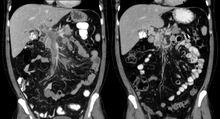

| Portal vein thrombosis seen with computed tomography. | |

The diagnosis of portal vein thrombosis is usually made by ultrasound, computed tomography with contrast or magnetic resonance imaging. D-dimer levels in the blood may be elevated as a result of fibrin degradation.